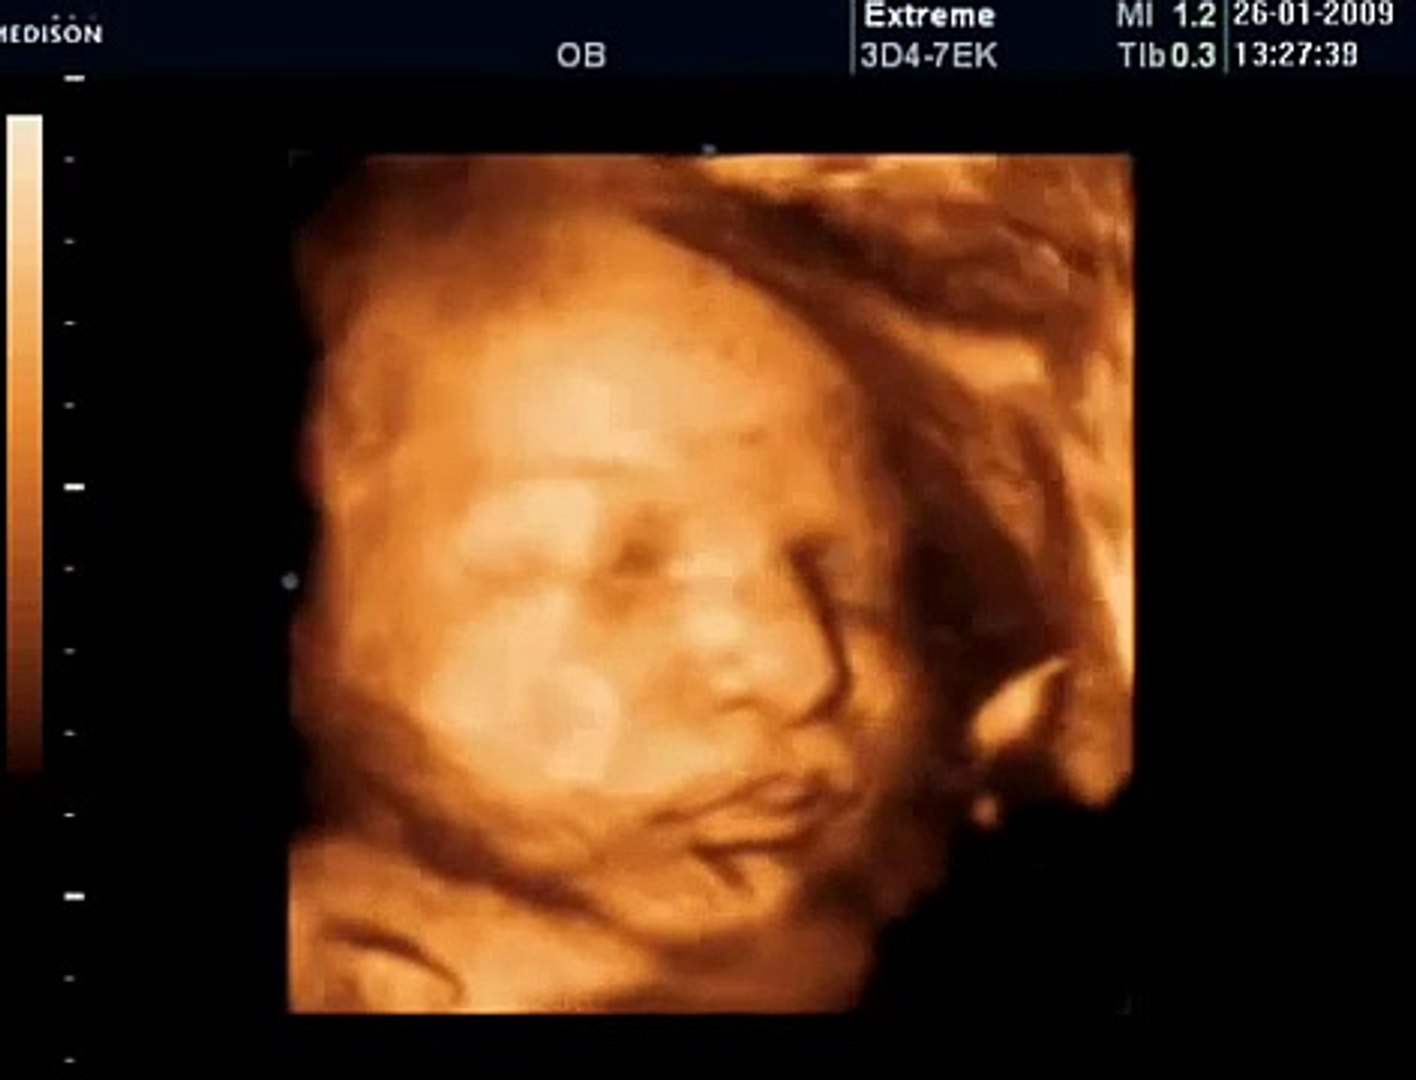

37 Haftalık Bebek Gelişimi

Hafta gebelikte bebeğin boyu ortalama 1 cm civarında artar kilo alımı değişir. 37 haftalık hamilelik itibariyle bebeğinizin boyu 50 santimetre kilosu ise 3 kg kadar oldu. Hafta gebelikte bebek gelişimi. Artık onu kucaklamak üzeresin her an doğabilir.

Haftada anne karnında bebek. Peki 37 haftalık gebelik döneminde bebeğin boyu kilosu ve gelişimi nasıl olmalı. Aşağıdaki tabloda 37 haftalık bebek kaç kilo olmalı. Bu hafta itibari ile bebeğin kilosu iyice artar ve bebek tam.

Boyum yaklaşık 48 50 cm arasında. Bu haftada bebeğinizin başının ve karın çevresinin ölçümleri eşittir. 9 aylık gebe olan 37 haftalık gebeliğin gelişimi tamamlanmıştır. 37 haftalık bebek gelişimi bebeğin pozisyonu ve doğum belirtileri hamileliğin sonlarına gelinmesiyle birlikte bebek artık iyice ağırlaşır ve anne zorluklar çeker.